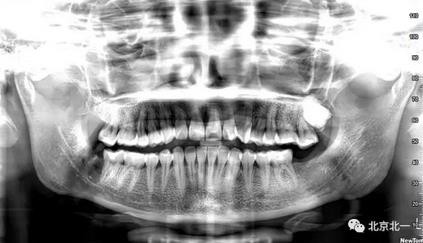

病例資料:一般情況,患者女性,28歲, 主訴:要求拔右側(cè)下頜智齒,檢查:右側(cè)下頜第三磨牙未見萌出, 拍片如圖。

圖一:CBCT顯示右側(cè)下頜水平骨埋伏牙,牙冠距離下牙槽神經(jīng)管接近。

圖二:自帶的CBCT顯示下牙槽神經(jīng)管貼著智齒走形。